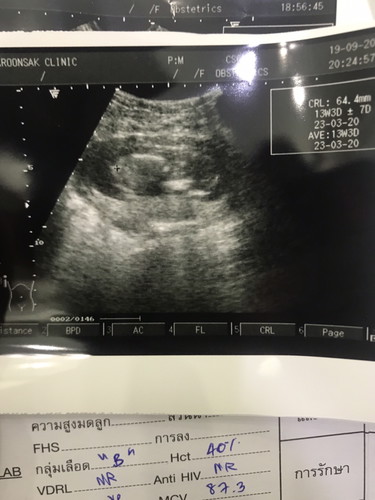

13w หมอถามอยากได้ผู้หญิงรึชาย เหมือนมีโด่ๆนะครับคุณแม่ แต่สายรกพาดเลยยังต้องรอลุ้นเดือนหน้านะ😄😄

3เดือนเพศยังไม่ชัดเจนค่ะส่วนมากหลัง4เดือนแต่ส่วนมากเพื่อความชัวร์หมอซาว์ดเพศตอน18-20วีคค่ะ

บ้านนี้ รู้เพศ ตอน 19+1วีค ส่วนในภาพนี้ หมอนัดเมื่อวาน ครบ23วีค พอดี ค่ะ จู๋โผล่ชัดมาก 😊😊 😂😂😊😊